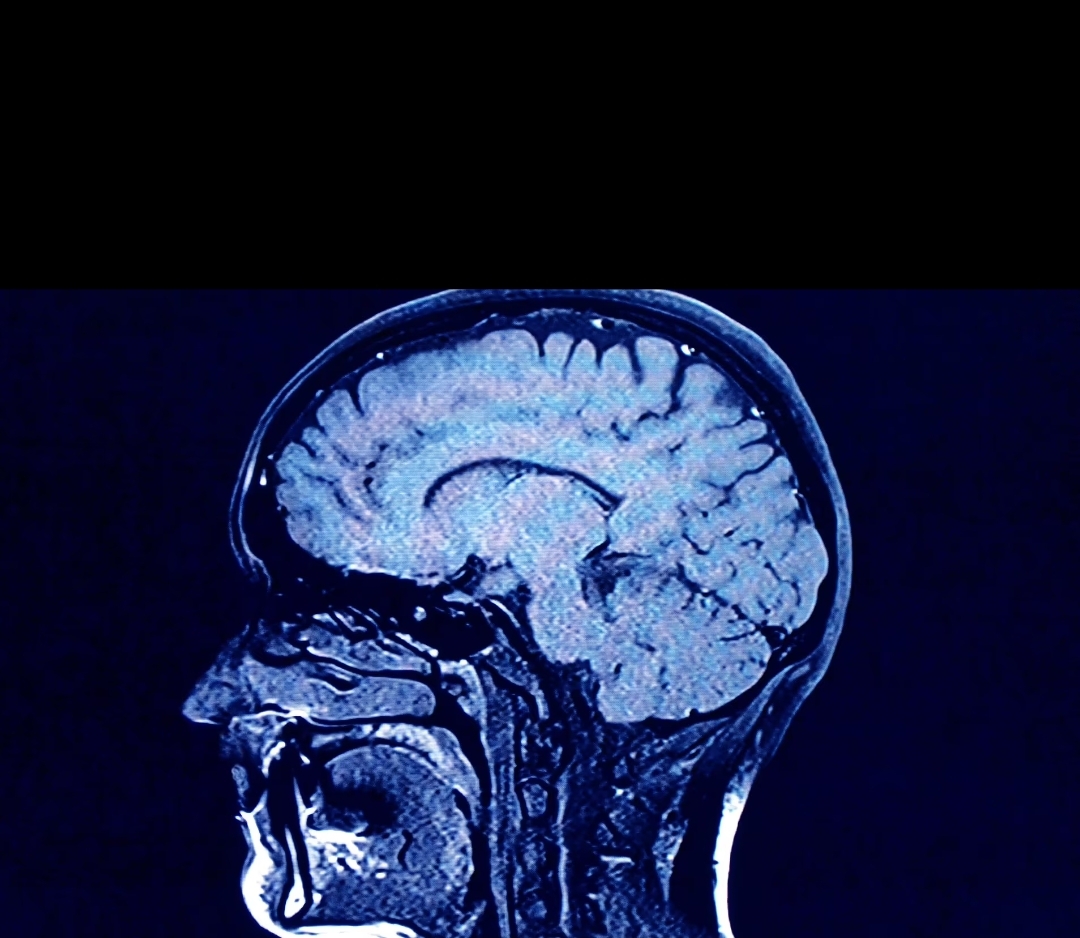

Beyin bu sistemin bir parçası değildir ve onun atık imha yolu, glimfatik sistem olarak bilinir. Karbon dioksit, hasarlı proteinler ve ölü hücreler gibi, enerji tüketen metabolik süreçlerin (vücudun düzgün çalışmasını sağlamak için vücutta sürekli çalışan tüm kimyasal süreçlerin) ürettiği atıkları temizler.

Ancak yaşlandıkça glifatik sistem bozulur ve bilişsel gerilemeye ve hafıza kaybına, ayrıca Alzheimer hastalığına ve bunamaya neden olan amiloid proteinleri ve tau düğümleri gibi atık ürünler birikir.

Uyku düzenindeki değişiklikler normal atık bertaraf sürecini de altüst edebilir. Uyurken CSF hücreler arasında daha serbestçe akar ve tüm glifatik süreç uyku sırasında optimize edilir.

Yeterli uyku alınamaması durumunda beyin omurilik sıvısı akışı bozulur ve nörodejeneratif hastalıklarla ilişkili atık ürünlerin temizlenmesi de bozulur.